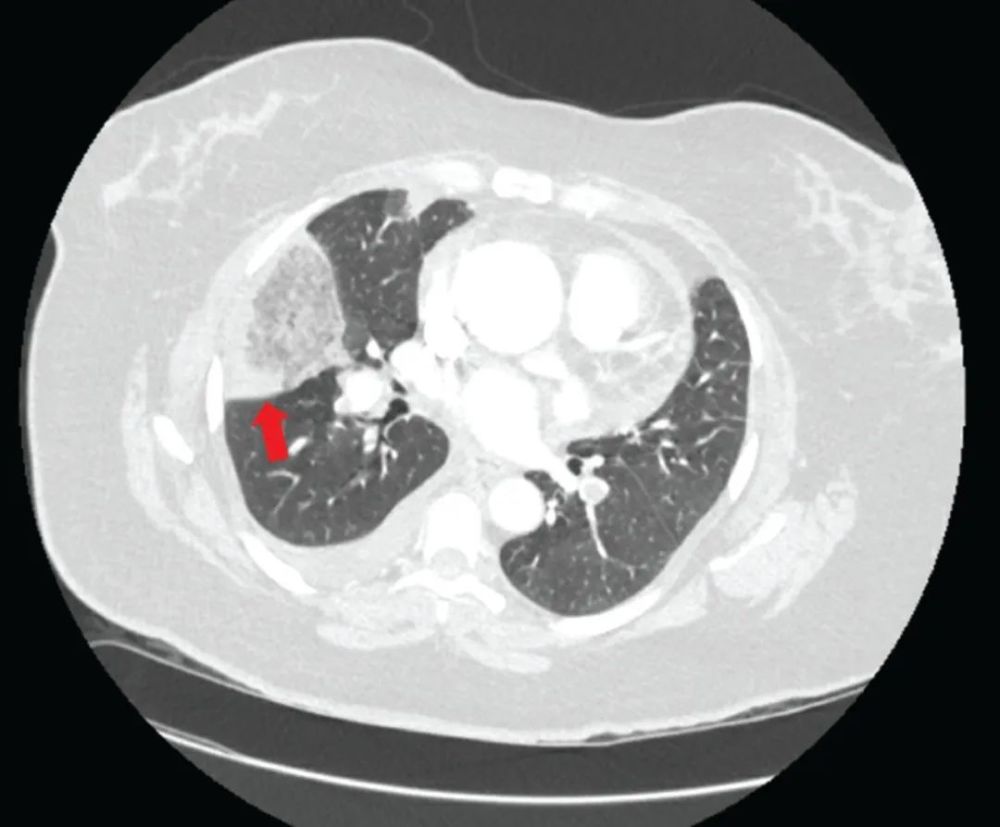

肺梗死的ct表现